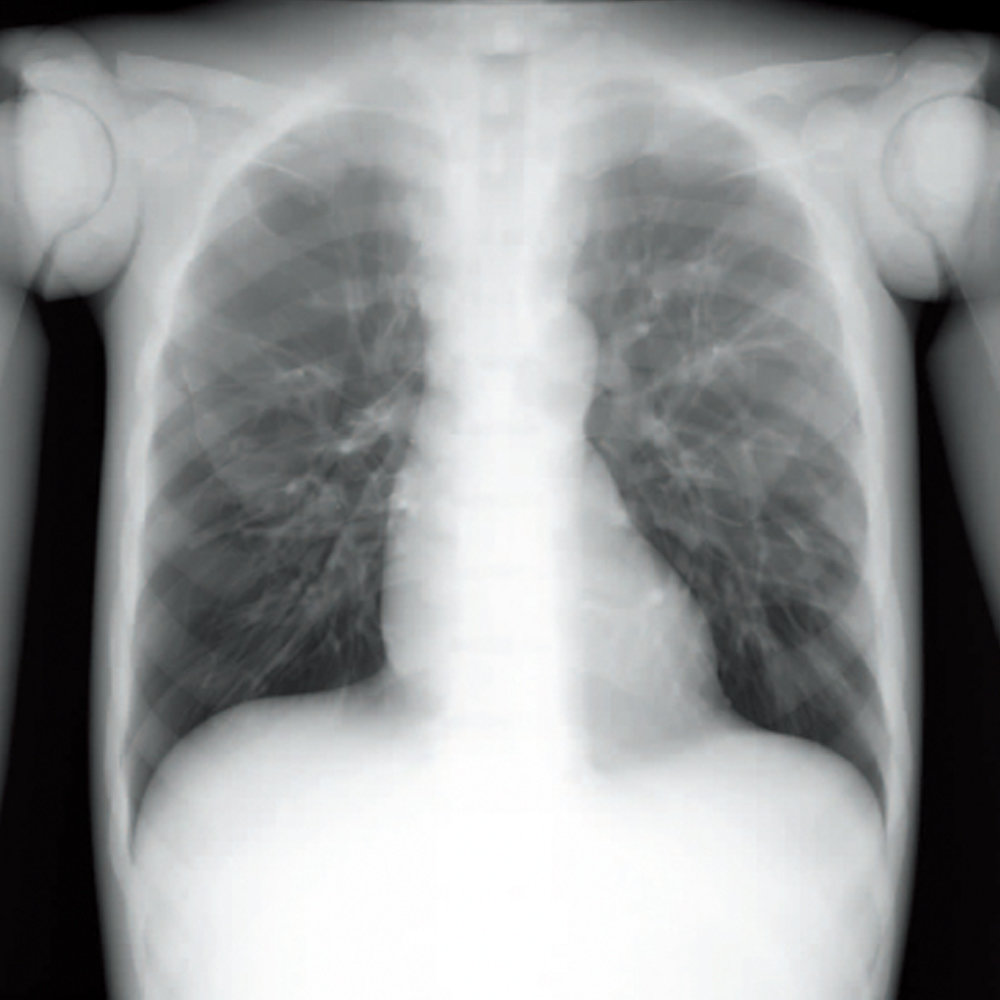

CT Whole Body Phantom - With Pathologies

1A unique, life size whole body phantom for CT provides a variety of educational application as well as visual evaluation in finding out optimal scanning conditions

| Training skills / Applications | Plain X-ray / CT /Basic patient positioning |